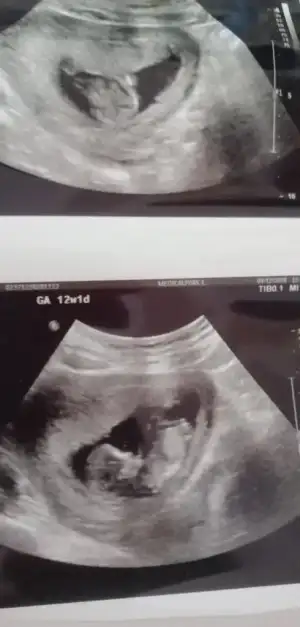

İkra meyra bana da bakarmısınız lütfen çook merak ediyorum bebeğimin cinsiyetini

Eklentiler

• IMG_20201209_181012.webp

IMG_20201209_181012.webp

20,5 KB · Görüntüleme: 57

• IMG_20201209_175916.webp

IMG_20201209_175916.webp

37,6 KB · Görüntüleme: 49

• IMG_20201209_175934.webp

IMG_20201209_175934.webp

22,1 KB · Görüntüleme: 50

Malesef başka görüntüm yok ilk kız siz dediniz inşallah öyledir 🤲🤲🤲🤲 bir hafta sonra randevum var ozaman yazarım foto yollarım

Bir hafta nasıl dayanacaksin, ben dayanamazdım, yani dayanırım da düşün düşün bir hal olurdum. :) prenses geliyordur insallah :)